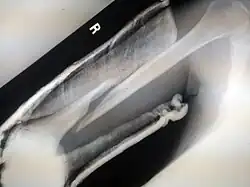

- Femoral fracture

- Crus fracture

- Tibia fracture

- Fibular fracture

- Combined tibia and fibula fracture